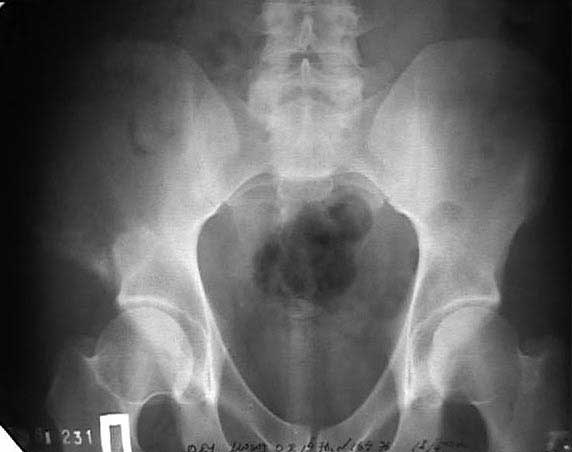

И 2010 год

Также структуру поражения кости можно увидеть на обычных рентгенограммах таза или Компьютерно-Томографических срезах. Трехмерные снимки, кроме красивой картины, не добавляют информации, и самым главным информативным является МРТ, которая покажет структуру ячеек.